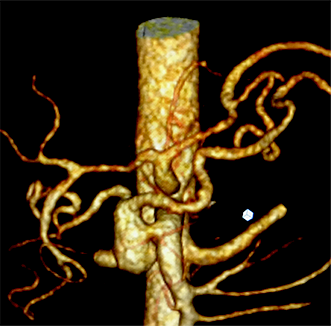

Cirurgia de Aneurisma de Aorta

Chamamos de aneurisma de aorta, a dilatação exagerada deste vaso. A doença pode acometer qualquer porção da aorta, desde sua saída do coração, até seu final, à altura do umbigo. Os aneurismas de aorta mais frequentes estão localizados no abdome, especialmente abaixo das artérias renais. Há basicamente duas formas de correção a fim de evitar a ruptura do aneurisma: a cirurgia e a correção endovascular com implante de uma endoprótese (assista ao vídeo). Na cirurgia para correção do aneurisma de aorta abdominal, com anestesia geral, o abdome é aberto pelo cirurgião vascular e o segmento dilatado da aorta é substituído por uma prótese tubular artificial, que se integra perfeitamente ao paciente.